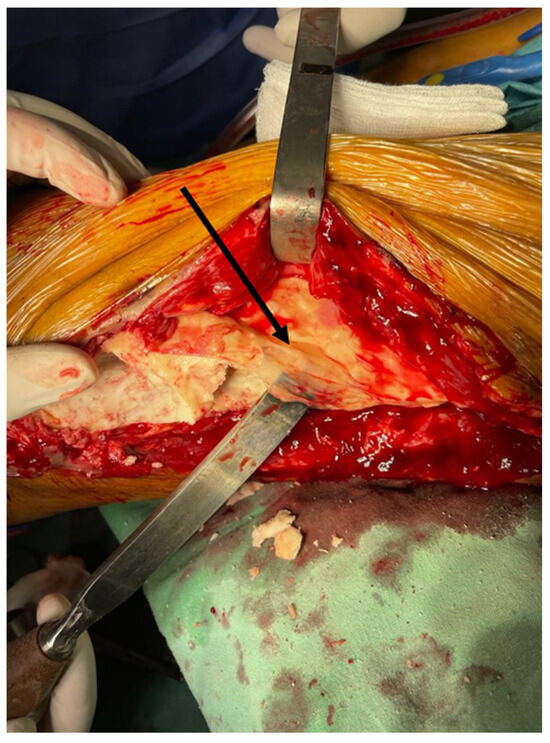

The Use of the Masquelet Technique in the Treatment of Pathological Distal Third Femoral Fracture Secondary to Chronic Osteomyelitis

2. Case Report